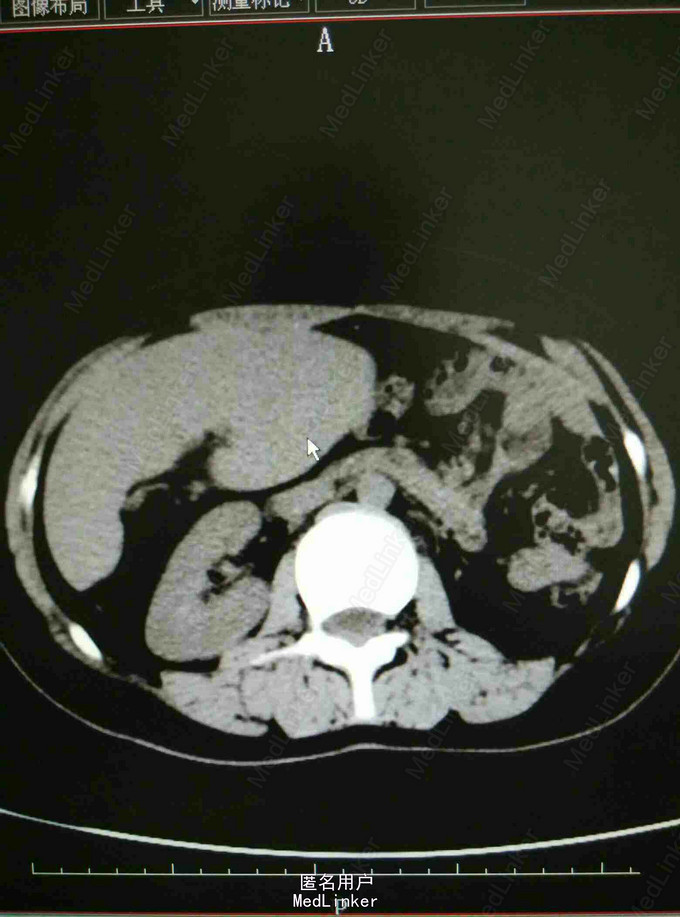

体检发现脾大一年余 患者于2014年04月体检时发现脾大、先天性膈疝。于2014年07月在中南大学湘雅医学院行胸膈疝修补术,具体术式不详,术后恢复良好。现患者为求进一步诊治入我院,门诊拟‘‘脾肿大 脾功能亢进’’收治住院。起病来,饮食睡眠可,精神良好,体重、体力无明显改变。青霉素过敏,余无特殊。

专科查体:腹平软,未见胃肠型及蠕动波,未见腹壁静脉曲张;全腹无压痛,反跳痛,肝肋下未及,胆囊未触及,右肋下脾脏可触及,Murphy征阴性;叩诊鼓音,未及移动性浊音,肠鸣音正常,肛门指检未检。入院总蛋白、白蛋白正常,白细胞2.50*10 9/L,红细胞4.36*10 12/L,血小板172*10 9/L,CT提示内脏移位,脾大,余检查无特殊。

入院诊断:脾机能亢进 处理:全麻下行腹腔镜下脾切除术,术后病理提示慢性脾瘀血。